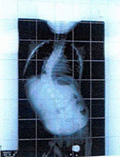

平成21年2月25日

装具して8度

レントゲン平成20年8月11日 レントゲン平成21年2月25日 レントゲン平成21年10月21日